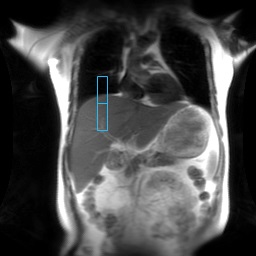

Figure 8. Tracker placement for Breath Hold selection Inspiration

Figure 9. Tracker placement for Breath Hold selection Middle

Figure 10. Tracker placement for Breath Hold selection Expiration

- The tracker should not overlay the thoracic wall nor the heart. It should not extend to the bottom edge of the liver.